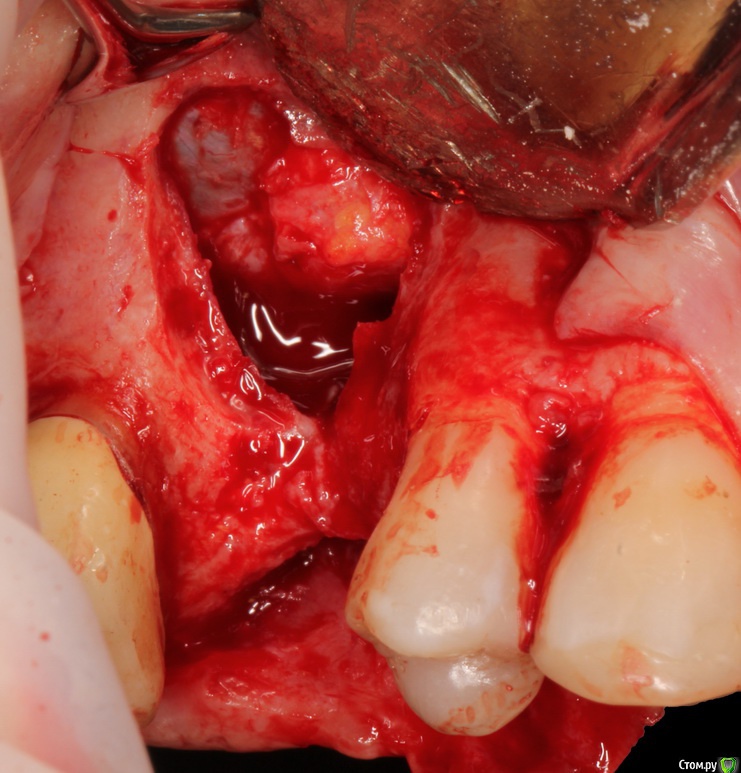

Bier Опубликовано 9 мая, 2017 Поделиться Опубликовано 9 мая, 2017 Коллеги, какие методы вы бы предложили? Передней стенки пазухи нет, ширины и высоты альвеолярного гребня нет.http://s018.radikal.ru/i506/1705/44/1ae64b3deac8.png Ссылка на комментарий

Bier Опубликовано 10 мая, 2017 Автор Поделиться Опубликовано 10 мая, 2017 Поговори с ней, очаруй своим шармом. Непростая работа, но можно решить без особых потерь.Карен, пациентка пришла ко мне за имплантатом. Она могла прийти в 10 других мест и сделать мост. Давайте обсудим хирургические перспективы такого кейса, ах да, забыл сказать: преддверия после пластики ОАС тоже нет. Ссылка на комментарий

колесников Опубликовано 10 мая, 2017 Поделиться Опубликовано 10 мая, 2017 6мес много,все в рубцах,сложнее раскрыть и после укрыть. Кт бы покрутить ещё... Конечно вы все уже сделали? У Radoslaw Jadach есть похожий кейс. https://www.facebook.com/permalink.php?story_fbid=1422863511106734&id=100001492961442Кстати про отсутствие преддверия и угрозу расхождения краев. Тот же Radoslaw Jadach ,со своим крокоайс ,предлагал ушивая перфорацию шнейдеровой мембраны стабилизировать швы фиксируя их на компактной пластинкевнутренним швом,позднее модифицировал и выводил шов наружу. Почему бы не стабилизировать лоскут таким образом? Т.е. зафиксировав его к щёчной стенке пазухи через пару перфорационных отверстий. И нет ,я так не делал. Все ещё в ожидании подходящего случая. Если решитесь попробовать-отпишитесь о впечатлениях. Ссылка на комментарий

Jurai Опубликовано 11 мая, 2017 Поделиться Опубликовано 11 мая, 2017 я подобное делала, но перфо меньше было и шире поле - отсутствовали 14,15,16,17, ОАС 16. Я в области 16 сделала расщепленный лоскут, от костных краев полнослойный. По краям перфорации обработала кость так, что фактически оставшаяся расщепленная часть лоскута висела на Шнайдеровой мембране - по сути расширила перфу, получила офигительный дефект в виде отсутствия дна и латеральной стенки. Мембрану подняла, и чтобы восстановить дно и стенку - Цитопласт с титаном, графт. Зашивала - чуть не до глазницы мобилизовала, натянула. И таки получилось вполне себе неплохо, через 6 мес поставила имплантаты, и работала с мягкими тканями. К сожалению, снимки не добыть уже - дело было 5 или 6 лет назад, в клинике уже не работаю. 3 Ссылка на комментарий

Bier Опубликовано 23 мая, 2017 Автор Поделиться Опубликовано 23 мая, 2017 господа, есть вертикальный дефект. С обычной коллагеновой мембраной такого результата тут не получить. Нужен каркас. Ну а что выбрать в качестве каркаса - уже остается на выбор клинициста. Ссылка на комментарий